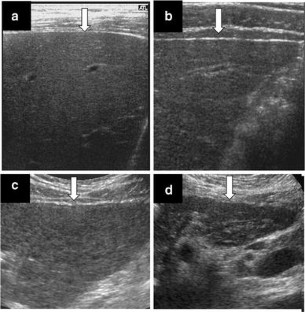

Fig. 2